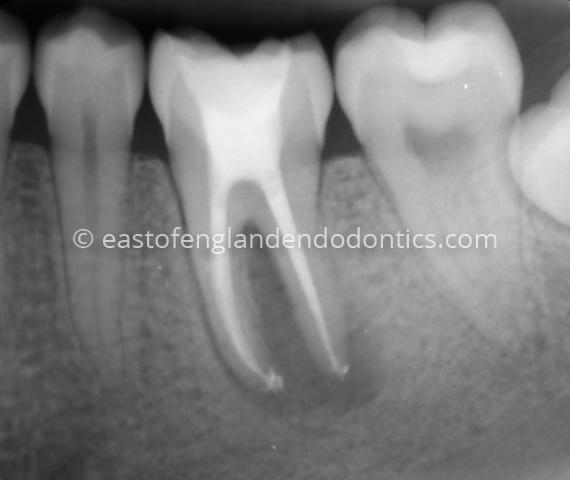

Case StudiesPre-operative radiograph LL6